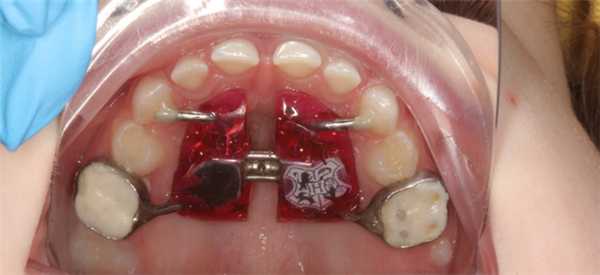

Классический аппарат состоит из винта хайрекс, пластмассового базиса, опорный колец на молочные моляры и направляющих к молочным к клыкам.

Но, конечно же, в зависимости от клинических ситуаций могут быть индивидуальные модификации. Например, при преждевременном удалении молочных зубов. В таких случаях опорные кольца изготавливаются на постоянные шестые зубы.

Ребёнок сам выбирает цвет и героя, который будет жить у него в полости рта.

Аппарат Хааса состоит из колец на первые постоянные моляры или вторые молочные моляры и дополнительных лапок на молочные клыки или колец на первые премоляры, а так же имеет пластмассовый базис с винтом Hyrex, который плотно прилегает к слизистой оболочке неба.

Чаще всего аппарат Хааса применяется в детской ортодонтии. Именно в данном возрасте мы можем влиять на рост челюстей, тем самым создавая место для постоянных зубов и корректируя прикус. Дети могут самостоятельно выбрать любимый цвет и картинку для аппарата. Результаты лечения более стабильны и прогнозируемы. Однако аппарат Хааса может применяться во взрослом возрасте. Так как костные структуры уже все сформированы, использование этого аппарата возможно только совместно с хирургически-ассоциированным послаблением небного шва. Показания к применению такие же, как и в детском возрасте. В результате, пациент получит широкую красивую улыбку.